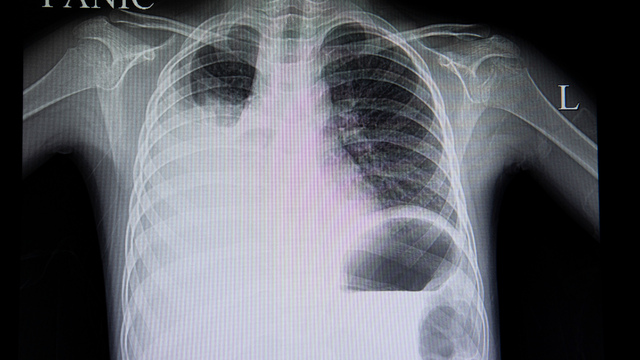

Bệnh phổi